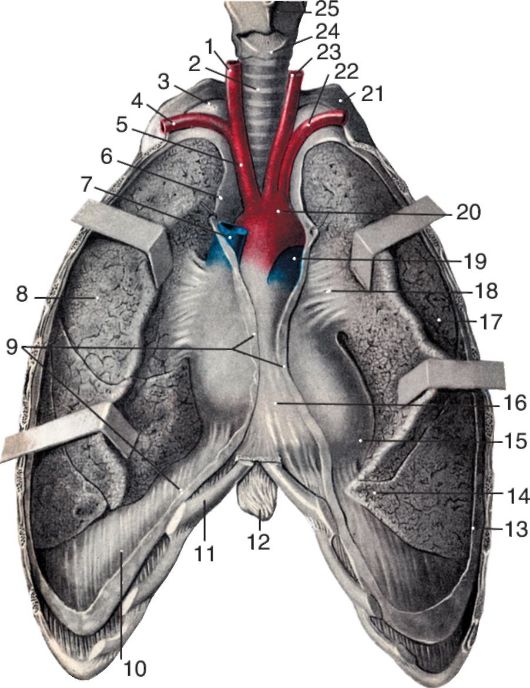

Анатомические изображения сегментов легких различных животных

Раздел: Другие животные